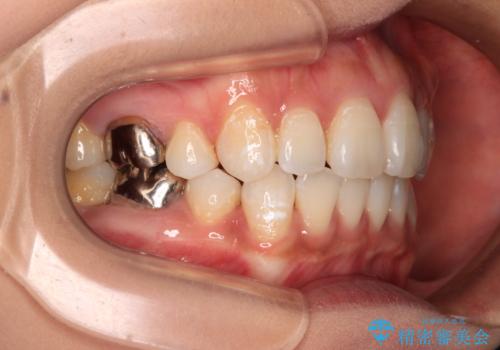

- 口元の閉じにくさを気にして来院された患者様です。

上下ともに歯列が前方に突出していたため、上下左右の第一小臼歯4本を抜去し、ワイヤー装置による矯正治療を行うこととしました。

舌の突出癖による影響もあったため、舌のトレーニングを並行して実施しました。

左下奥歯にむし歯が認められるため、矯正治療後にセラミックインレーにて修復治療を行うこととしました。